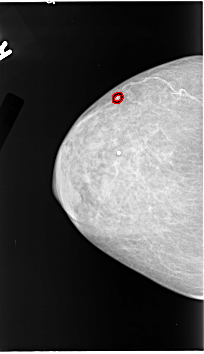

B_3130_1.RIGHT_CC

RIGHT_CC LINES 4592 PIXELS_PER_LINE 2640 BITS_PER_PIXEL 12 RESOLUTION 50 OVERLAY

FILE: B_3130_1.RIGHT_CC.OVERLAY

TOTAL_ABNORMALITIES 1

ABNORMALITY 1

LESION_TYPE CALCIFICATION TYPE PLEOMORPHIC DISTRIBUTION CLUSTERED

ASSESSMENT 4

SUBTLETY 2

PATHOLOGY BENIGN

TOTAL_OUTLINES 1

BOUNDARY